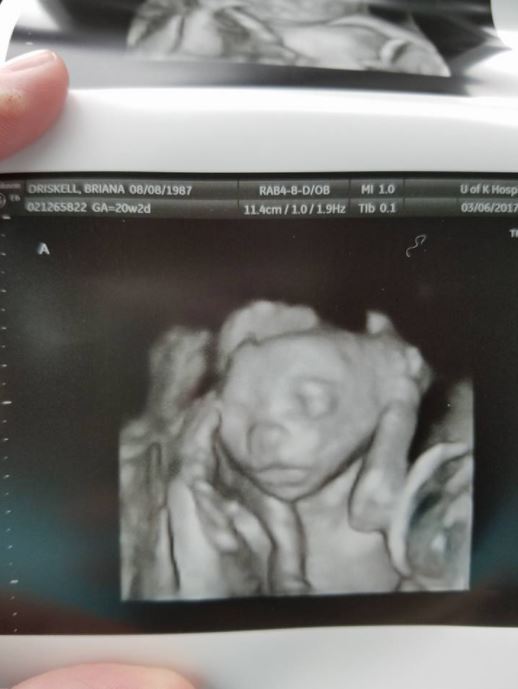

透過超音波畫面可以看到,布萊安娜肚子裡竟然出現五個胎兒!

女人光懷一個孩子就已經很辛苦,更不用說一次懷上五個,布萊安娜從懷孕第22週就住院,期間無法下床直到生產,「我一直試著想讓寶寶們待在子宮裡至少到30週。」但到了第28週,她就因為妊娠 毒 血 症,必須緊急剖 腹 產。

2017年5月2日,布萊安娜生下了柔伊(Zoey)、達柯塔(Dakota)、霍琳(Hollyn)、艾許爾(Asher)和賈文(Gavin),總共三個女兒和兩個兒子,寶寶們雖然早產,幸好身體狀況沒有問題。「當我終於看到他們時,忍不住哭到無法呼吸。我仍然不敢相信我終於成為母親了,這真的好不真實。」